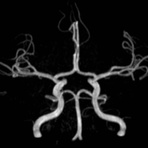

- MR-Angiografie ohne Kontrastmittel

- Time of Flight (TOF)-Angiographie

- Phasenkontrastangiographie (PCA). Geeignet zur Quantifizierung Stenose-/Insuffizienzgrad z.B. bei Herzklappen, falls echokardiographisch die Untersuchungsbedingungen eingeschränkt sind.

Je nach Fragestellung und Körperregion Gefäßdarstellung ohne Kontrastmittel bei Kontrastmittelunverträglichkeit oder terminaler Niereninsuffizienz möglich.

- MR-Angiographie mit Kontrastmittel

- Erfassung arterieller und venöser Gefäße/Bypässe aller Körperregionen mit 3D-Rekonstruktion

- je nach klinischer Fragestellung zeitaufgelöste MR-Angiographie (4D-MRA) z.B. bei Frage arteriovenöse Fistel/ Shunt oder Darstellung Unterschenkelarterien vor geplanter Bypassoperation.